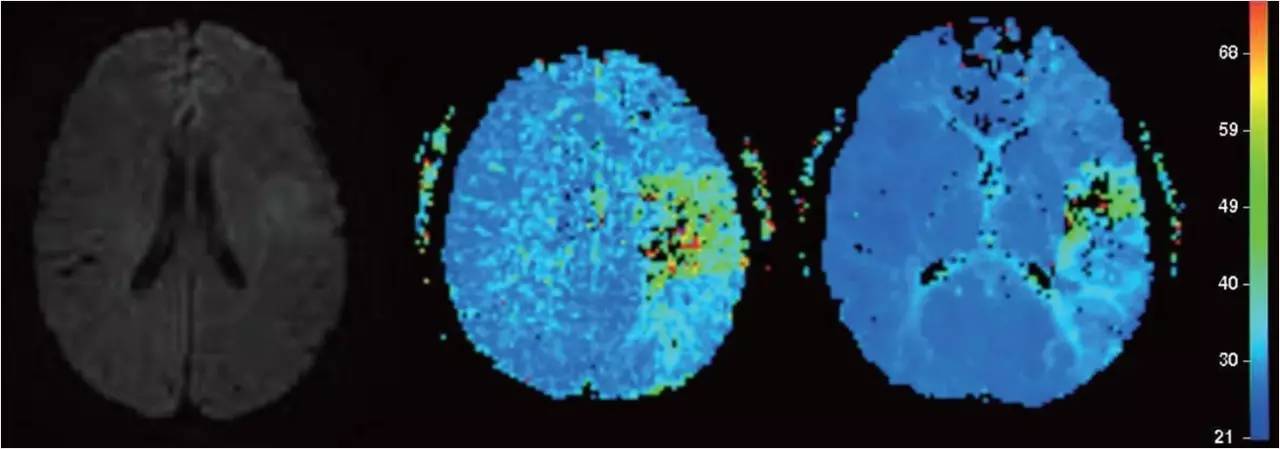

》男性,47岁,SIE;

》UCG:主动脉瓣关闭不全,赘生物;

》突发言语不能、右侧肢体活动不能;

》查体:运动性失语,右侧肌张力低,右侧肌力0级,右侧巴氏征阳性 。NIHSS评分18分;

》CT:颅内未见出血;

》DSA:左侧大脑中动脉闭塞。

术前

术后

》意识清楚,言语流利,四肢活动自如;

》四肢肌力Ⅴ级;

》术后24小时NIHSS评分:0分;

》5天后主动脉换瓣术;

》90天mRS评分0分。